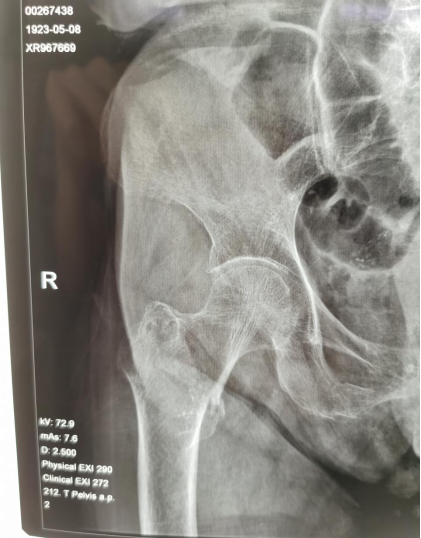

上图为老人术前X线,可见右股骨粗隆间骨折

经过详细询问病史、系统体格检查,并综合检验及影像学检查结果,周世峰教授认为,老人99岁高龄,且合并双肺气肿、肺大疱、脑梗死等基础疾病,心电图提示老人有心房颤动,检验结果提示老人有贫血、低蛋白血症、低钙低钾血症,选择手术治疗有很大风险。急诊急救中心主任侯利民教授组织心内科、麻醉科多学科会诊,经过周密研判,决定周世峰教授为老人实施PFNA内固定术。